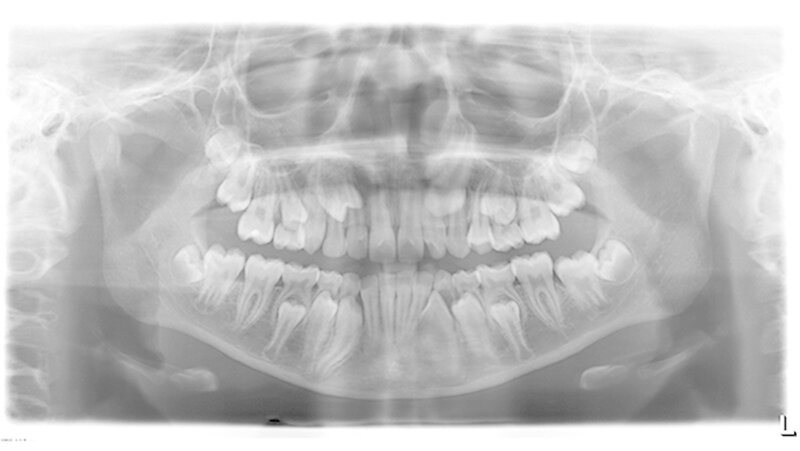

Dieser Fallbericht zeigt eine Patientin mit einer Transposition und multiplen verlagerten Zähnen, die mithilfe eines Gaumenimplantats eingeordnet wurden. Das Mädchen stellte sich im Alter von 13,7 Jahren in unserer Praxis vor. Bei der klinischen Untersuchung fiel die Persistenz mehrerer Milchzähne auf. Der Zahn 13 war distal des Milchzahns 53 durchgebrochen.

Das OPG zeigte eine Dentitio tarda, eine mesial-exzentrische Verlagerung der Zähne 14 und 23 mit Persistenz der Milchzähne 53 und 63 sowie eine Transposition der Zähne 13 und 14. Alle bleibenden Zähne inklusive der Weisheitszähne sind angelegt. Zudem bestand eine mesial-exzentrische Keimlage der Zähne 15 und 25.

Anhand eines DVT konnten Wurzelresorptionen an den seitlichen Schneidezähnen ausgeschlossen und die genaue dreidimensionale Lage der retinierten und verlagerten Zähne 14 und 23 genauer beurteilt werden. Die Auswertung des FRS ergab eine skelettale Klasse I mit bignather Orthognathie bei mesofazialer Schädelstruktur.

Im Rahmen der Modellanalyse ergaben sich folgende Befunde: Im Oberkiefer lagen außer der Transposition der Zähne 13 und 14 multiple Rotationen und Kippstände vor. Die Unterkieferfront wies einen Engstand auf. Im Molarenbereich lag beidseits eine Distalokklusion von ¼ Prämolarenbreite vor. Der Overjet betrug 2 mm, der Overbite 3 mm. Die Zähne 22/33, sowie 24/74 wiesen eine Kopfbissrelation auf.